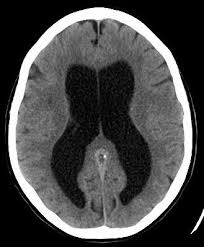

Hydrocephalus Wikipedia The Free Encyclopedia Ct Scan A Level Physics Health Blog